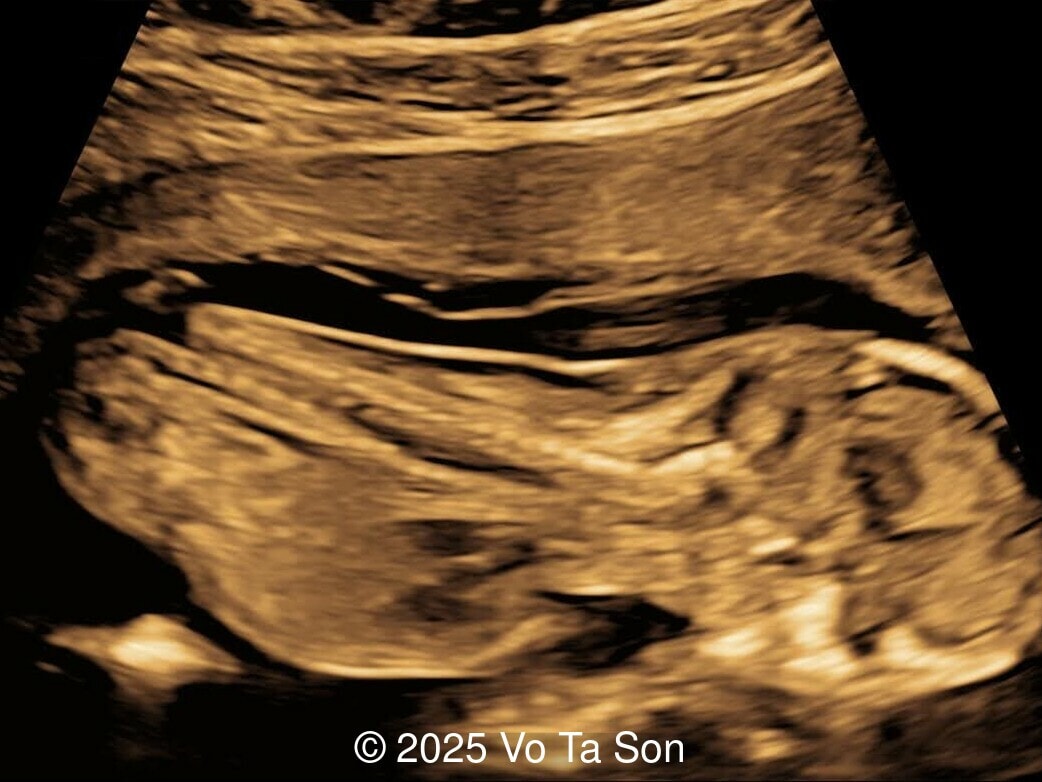

• Open spina bifida in the sacral region with dry brain sign, crash sign, BS/BSOB >1, and a lesion at the sacral coccygeal spine. The spinal lesion observed in the sacral region is characterized by a posterior vertebral arch defect and a protruding meningeal sac.